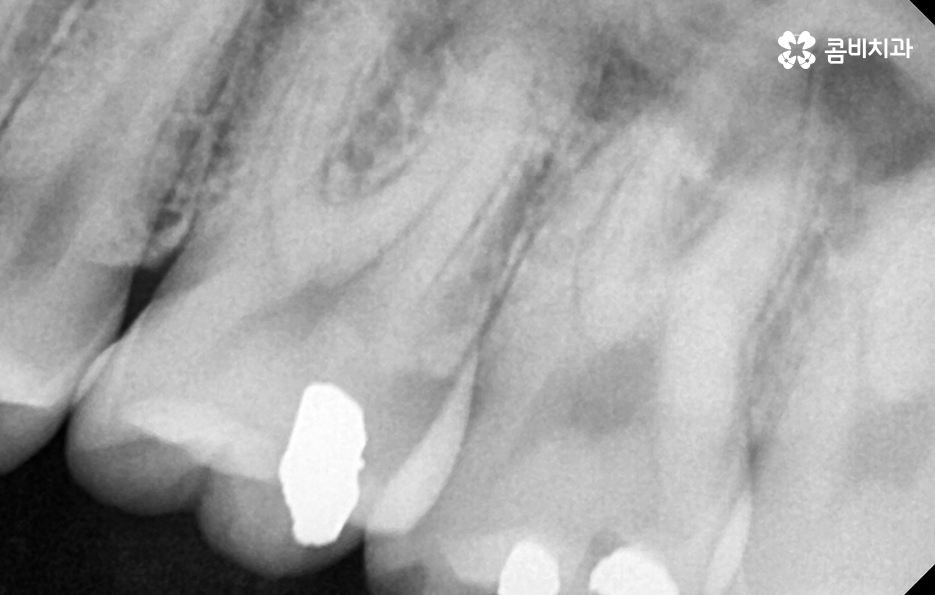

어금니 충치로 인해 치아가 파절된 경우에는 아무래도 치아의 손상이 큰 경우가 많은 편이기 때문에 심한 파절의 경우에는 신경치료 후 크라운을 씌워도 수명을 오래 유지 못하는 경우도 있는데요

치아를 살릴 수 있는지 아니면 발치 후 임플란트로 이어지는 것인지 정확하게는 치과에서 진단을 정확히 받아보셔야 하겠지만 기본적으로 치아의 수명을 좌우하는 조건에 있어서 자연치아가 잔존하는 정도 그리고 치아 뿌리의 손상 여부에 따라 자연치아를 보존할 수 있는지 아니면 발치 후 임플란트를 해야할지 크게 갈리는 요소가 될 수 있어요

어금니 충치 깨짐이 발생했을 때 빠른 치료를 해야하는 것도 치아의 뿌리 손상과 자연치아를 되도록 보존하는 치료를 하기 위해서 치료 적기를 놓치지 않아야만 자연치아 보존률을 보다 높일 수 있는 것이며 치아 뿌리 쪽 손상이 심하면 결국 발치를 해야 하기 때문에 치아 손상이 발생 했다면 빨리 치과부터 가보시길 권하고 있는데요